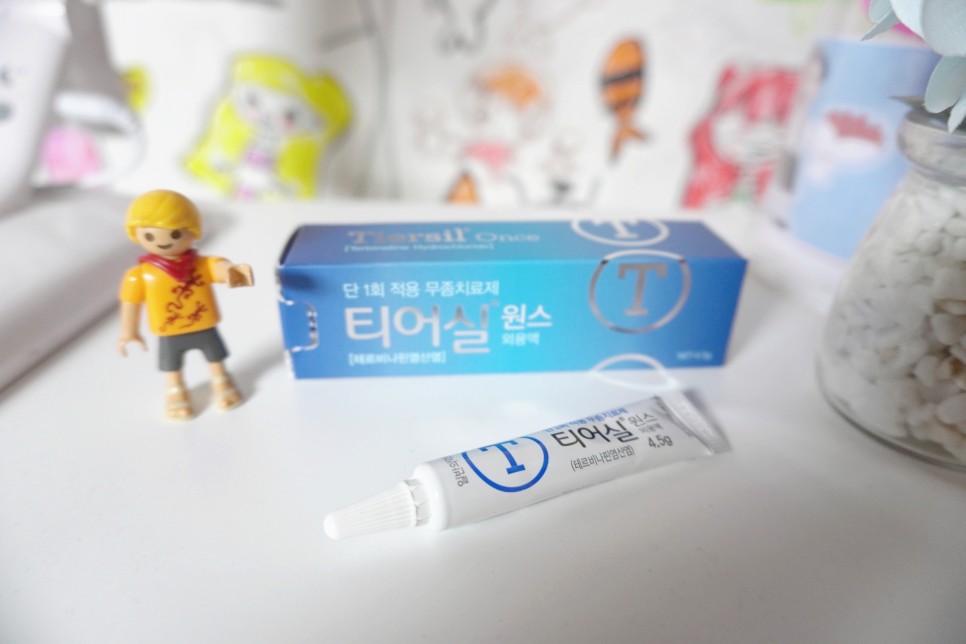

송가 무좀약이에요~ 이왕이면 큰 무좀약으로~ 겉보기에는 작지만 효과는 강력하기를 기대합니다~

단 1회의 도포만으로 빠른 효과를 얻을 수 있다고 적혀 있습니다!지금부터 시작하자는 단계이므로, 이번만 바르는 것으로 올해는 무좀 없이 지나갔으면 합니다.

티어씰 원스가 단 한번의 사용으로 효과를 볼 수 있는 것은 자체 특허를 출원한 실리콘 필름막 기술 덕분입니다.약을 바르면 실리콘 필름이 형성되어서 오랫동안 무좀균을 살균해서 치료해준다고 하네요.한번 바르면 13일간 약효가 지속된다고 합니다.